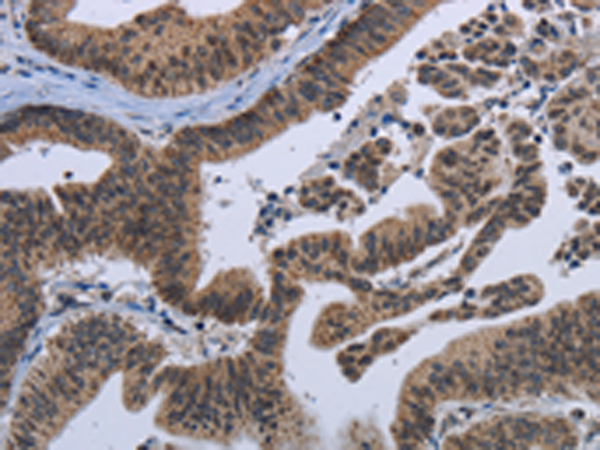

分类: 科研抗体货号: P08291别名: PICH; RAD26L应用: IHC反应种属: Human